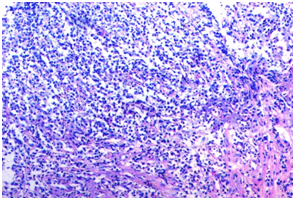

Figure 11 Poorly differentiated squamous cell carcinoma (H&E, 100X).

In our study, out of 45 cases positive for malignancy on biopsy in upper GIT, 36(80%) cases were squamous cell carcinoma(SCC), 7(16%) cases were adenocarcinoma, 1 was of neuroendocrine tumour (2%) and 1 case was of poorly differentiated carcinoma(2%). Out of 39 cases positive for malignancy on cytology, 20(51%) cases were squamous cell carcinoma, 3(8%) were adenocarcinoma, 1(3%) was of small cell carcinoma, 4(10%) cases were poorly differentiated carcinoma and 11(28%) were unspecified carcinoma. Studies by Kaur et al.11 and Vidyavathi et al.5 also showed squamous cell carcinoma being the most common malignancy in upper GIT.